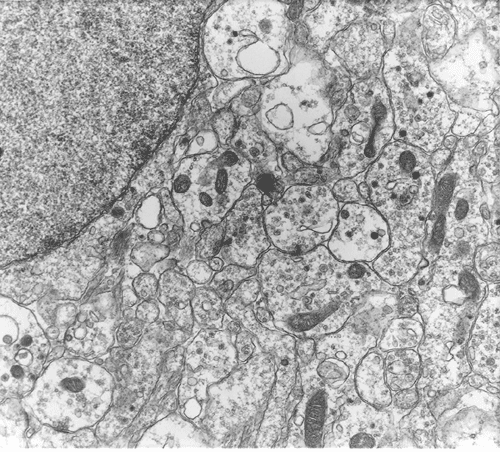

Panel A and B are low-magnification photomicrographs featuring solid sheets of isomorphous, small round to ovoid neoplastic cells with a delicate but rich vascular network. There are also intervening irregular patches of fibrillary neuropils. At high-magnification, the tumor cells appear as fairly uniform round to polygonal cells with perinuclear halo (Panel C). An island of neuropil is present in Panel D. The tumor cells are immunoreactive for synaptophysin (Panel E). The tumor cells were not immunoreactive for neurofilament proteins. At the ultrastructural level, the neoplastic cells contain numerous cell processes filled with vessicles and dense core granules (Panel F and G). Dense core granules and vescicles in high-mangification are shown in Panel H. The vesicles have structures similar to that of the synaptic vesicles, a feature of neuronal differentiation.

Ultrastructually, central neurocytomas have features of neuronal differentiation that include delicate cytoplasmic processes, microtubules, dense core granules and synaptic bouton-like structures. Intermediate filaments are exceptional. Dense-core granules of 60-160 nm are abundant. Clear vesicles of 40-60 nm of the pre-synaptic type and specialized syanptic junctions can also be seen 1. Neurocytomas also bear immunoactivity for synaptophysin. Immunoreactivity for chromogranin and neurofilament proteins is usually lacking. Slightly more than half of the cases in one study express a photoreceptor antigen 5. Reactive astrocytes, often in the form of stellate shaped cells with long cytoplasmic process, are well demonstrated by immunohistochemistry for glial fibrillary acidic protein (GFAP).